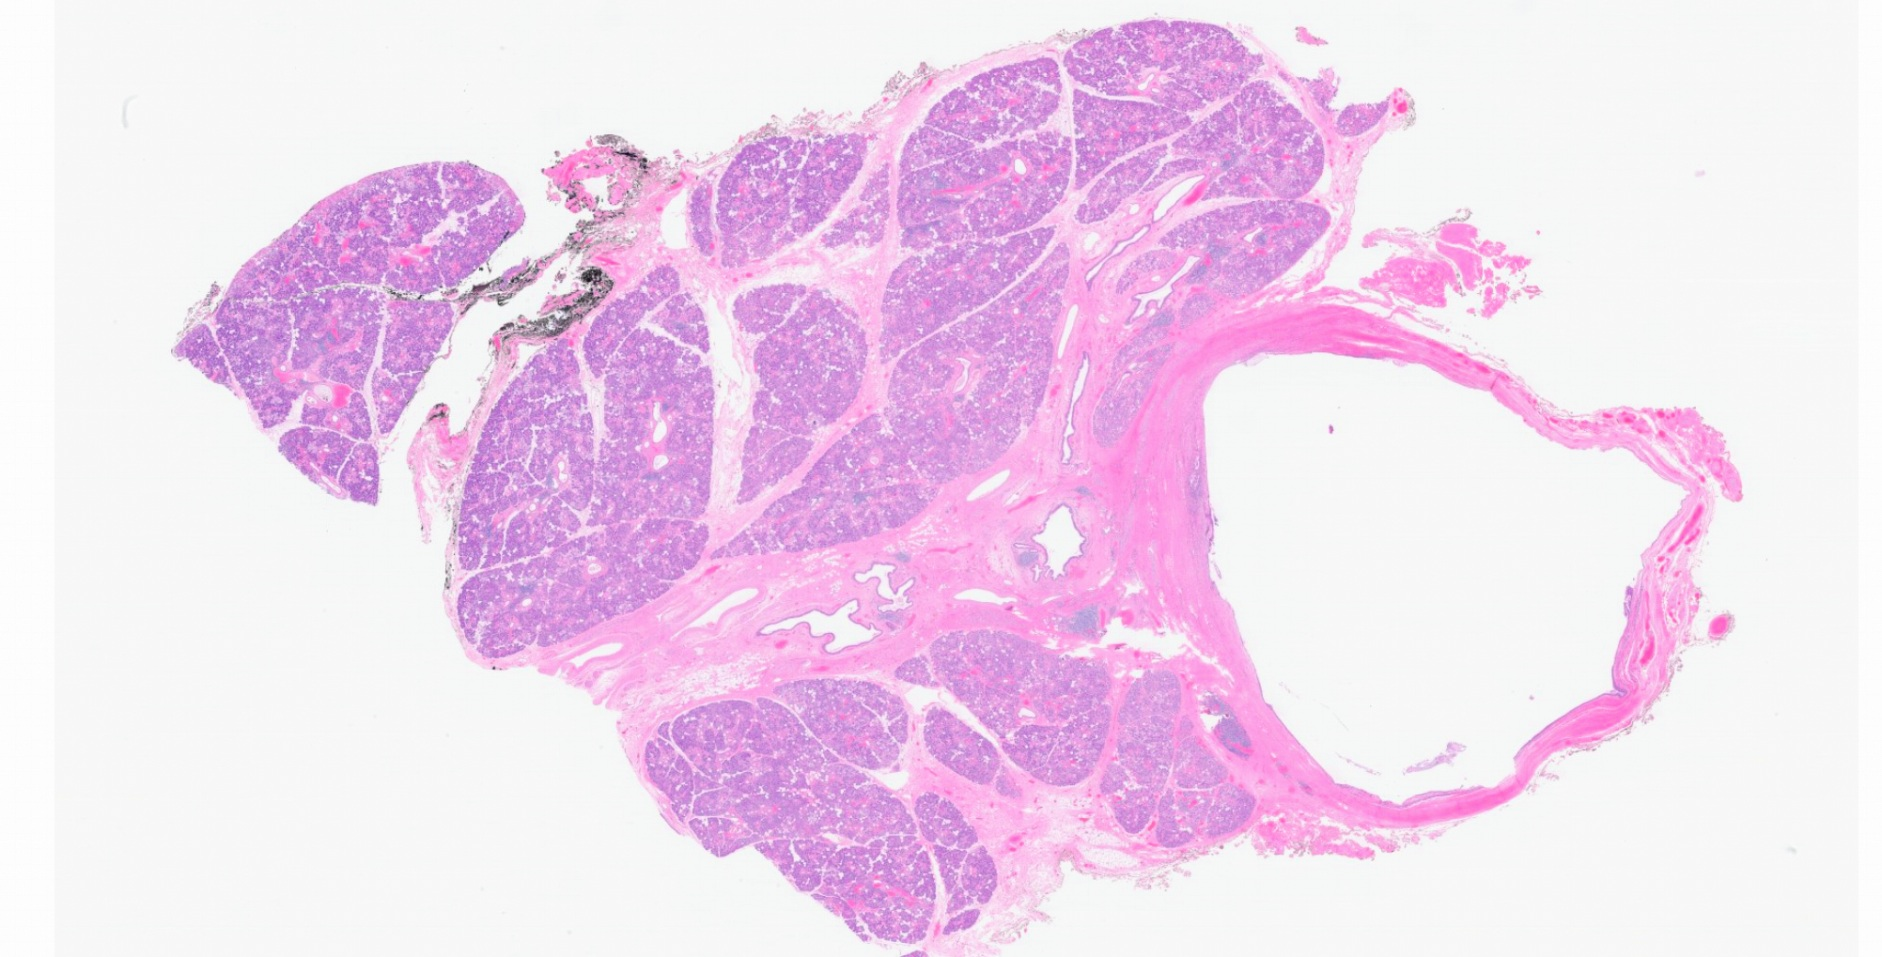

Outcome and follow-up. The patient’s submandibular gland was successfully removed and the sialolith was extracted. The surgical pathology demonstrated left submandibular excision with sialadenitis and sialolithiasis (Figures 3 and 4). Pathology was negative for neoplasm in the gland, which measured at 29 mm by 37 mm by 17 mm. Findings for the sialolith showed a single tan-white friable calculus that is present within a dilated ductal structure. The sialolith measures 11 mm in greatest dimension.

Figure 3. Dilated salivary duct with attached salivary glands (hematoxylin-eosin [H&E], original magnification × 0.6). Histological sections demonstrate focal epithelial ulceration of this grossly identifiable dilated duct associated with periductal fibrosis and chronic lymphocytic infiltrate.